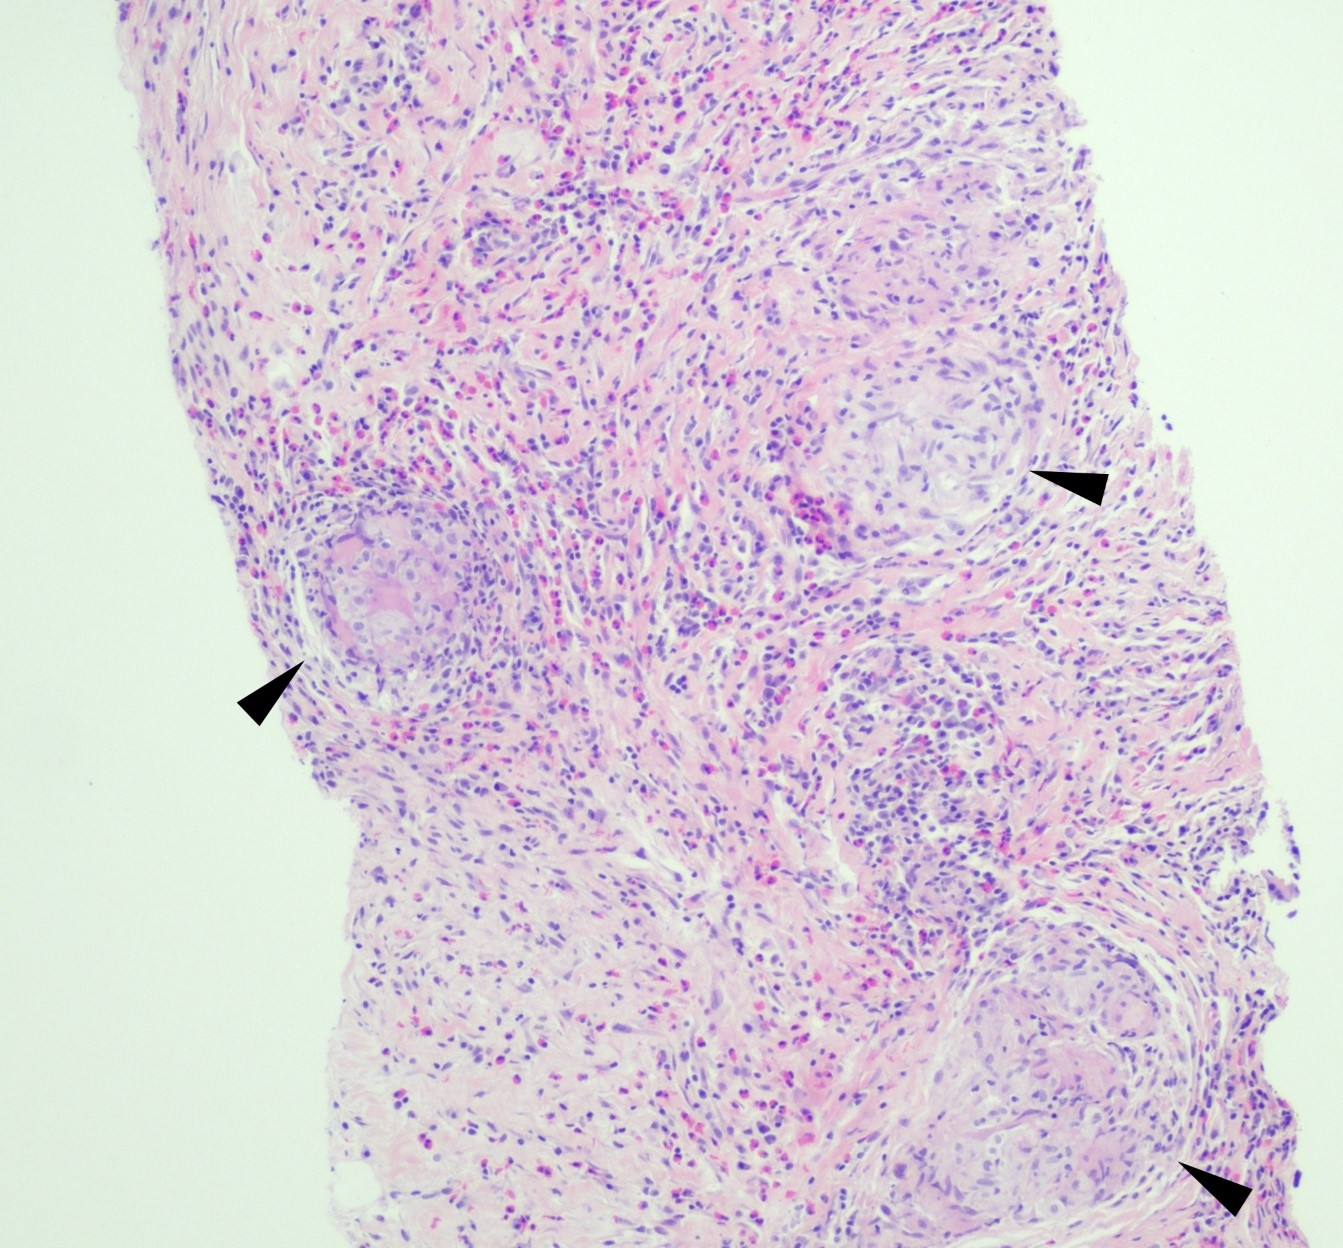

Figure 1. Core biopsy of omental tissue revealing granulomatous inflammation and diffuse eosinophilic infiltrate in a background of chronic inflammation, lymphocytes and fibrosis. Arrows indicate granuloma formation (H&E, 100x).

A 59 year old female presented with a one-month history of generalized abdominal pain, difficulty breathing, and early satiety. She was previously seen at an external facility and found to have liver hypointensity and abdominal distension which were concerning for liver cancer. Social history included travel to Sacramento and California deserts for hiking in the last few months. CT of the abdomen and pelvis demonstrated extensive peritoneal carcinomatosis with no primary etiology and a right hepatic lobe focus. MRI revealed diffuse omental caking and peritoneal thickening consistent with peritoneal carcinomatosis. Hepatic lesions also seen on MRI were consistent with hemangiomas. Laboratory evaluation was positive for Hepatitis B virus infection along with elevated liver enzymes (AST and ALT), CA-125, and normal levels of CEA. Paracentesis was performed removing 3 liters of yellow, cloudy fluid. Cytology demonstrated benign mesothelial cells, macrophages, and mixed inflammatory cells with a lymphocytic predominance in the peritoneal fluid. No malignant cells were identified. Initial aerobic, anaerobic, mycobacterial, and fungal cultures were negative. Serum Cryptococcus neoformans antigen testing was also negative. Ultrasound-guided core biopsy of the omental mass was performed; however, tissue was not sent for culture. Histopathology revealed granulomatous inflammation with eosinophilic infiltrate (Figure 1). A singular spherule was highlighted by GMS stain (Figure 2).  Fungal serology via complement fixation for Coccidioides was positive (titer: 1:8) while Blastomyces, Histoplasma, and Aspergillus serologies were negative. The patient was subsequently managed on fluconazole.